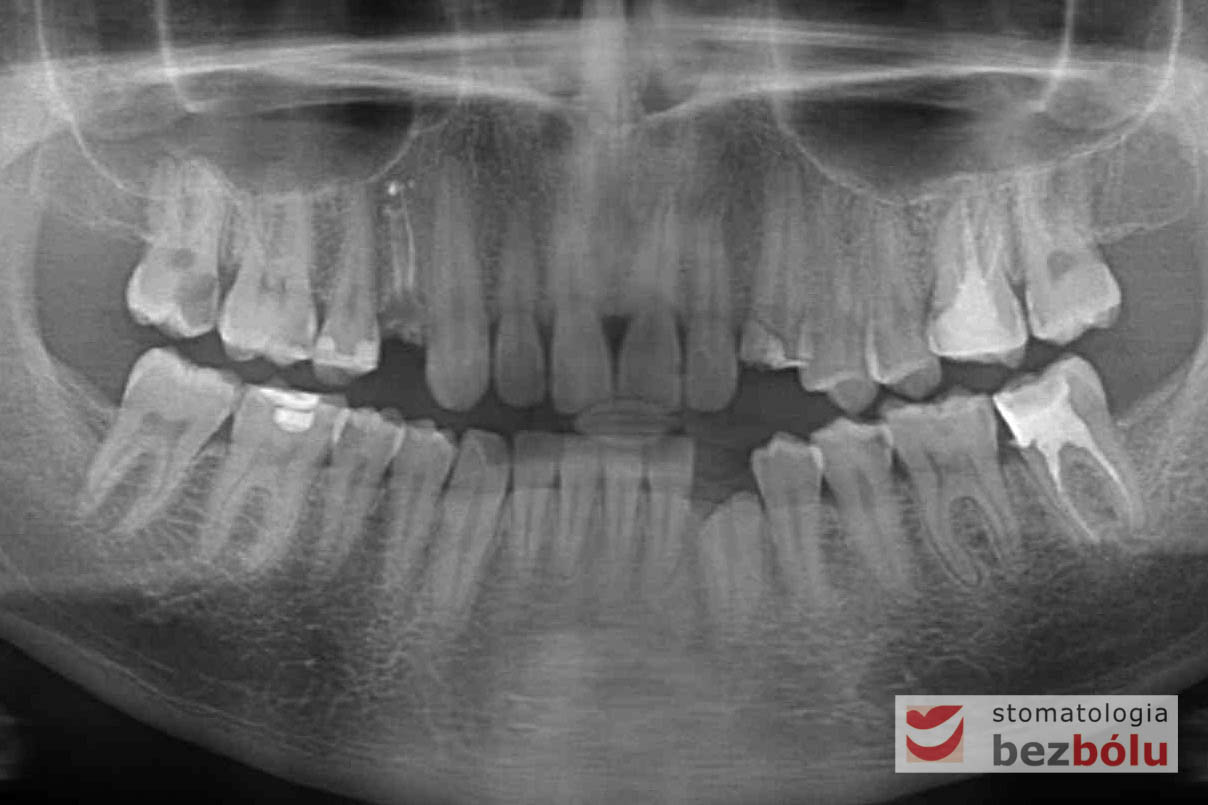

Po zakończeniu procesu gojenia wyrostka zębodołowego, wykonano diagnostykę radiologiczną z zastosowaniem tomografii wiązki stożkowej (CBCT) w celu oceny ilości oraz jakości tkanki kostnej, zarówno w miejscach poekstrakcyjnych, jaki i w pozycji górnego prawego przedtrzonowca. Ponadto pobrano wyciski, oddające sytuację kliniczną w jamie ustnej pacjenta, który zdecydował się na metodę implantacyjną, wykorzystującą nawigację komputerową, z zastosowaniem protokołu MGuide firmy MIS. Procedura ta polega na cyfrowym zaplanowaniu pozycji implantów, a następnie wykonaniu w technice druku 3D szablonu chirurgicznego.Taka metoda pozwala wyeliminować konieczność odwarstwiania płatów, zmniejszając przy tym pozabiegowe dolegliwości. Usprawnia jednocześnie pracę operatora, dokładnie pozycjonując wszczep w pożądanej pozycji. Kolejnym krokiem było przesłanie skanów modeli gipsowych oraz tomografii do siedziby MCenter w Berlinie, gdzie wysoko wyspecjalizowani technicy, dysponujący najnowszą technologią cyfrową, precyzyjnie wykonali szablony nawigacyjne, stosowane podczas zabiegu implantologicznego.

Procedurę chirurgiczną rozpoczęto od sprawdzenia przylegania szablonów do zębów pacjenta oraz znieczulenia miejscowego. W kolejnym kroku, przy pomocy specjalnie przeznaczonego do tego celu zestawu wierteł, wypreparowano krążki dziąsła punktowo odsłaniające kość a następnie poprzez tuleje prowadzące, z najwyższą precyzją, opracowano łoże implantu. Kulminacyjny moment zabiegu, czyli wprowadzenie wszczepów MIS C1 również odbyło się poprzez szablon, gwarantując precyzyjną lokalizację implantów. Zwieńczeniem całej procedury było przyszycie uprzednio wypreparowanych krążków śluzówkowo-okostnowych. Tuż po zabiegu, celem weryfikacji poprawnej pozycji implantów, wykonano zdjęcie ortopantomograficzne. Podczas wizyt kontrolnych, pacjent nie skarżył się na żadne dolegliwości bólowe, nie wystąpił obrzęk, a zreponowane we właściwych miejscach fragmenty dziąsła nie wykazywały oznak martwicy, co świadczyło o ich ponownym ukrwieniu i wgojeniu się. Wszystkie te przesłanki jasno wskazują na skuteczność zastosowania techniki komputerowej nawigacji w implantologii.